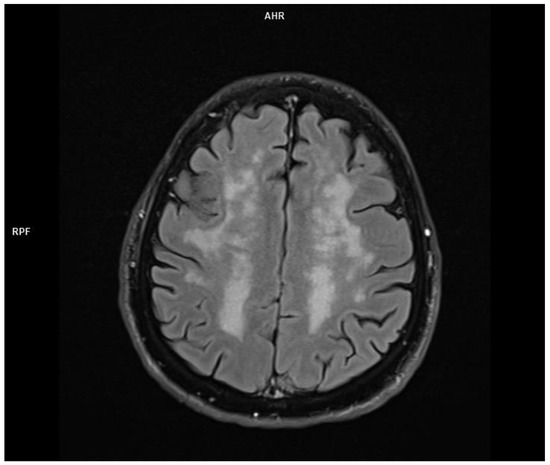

2.1. Patient 1